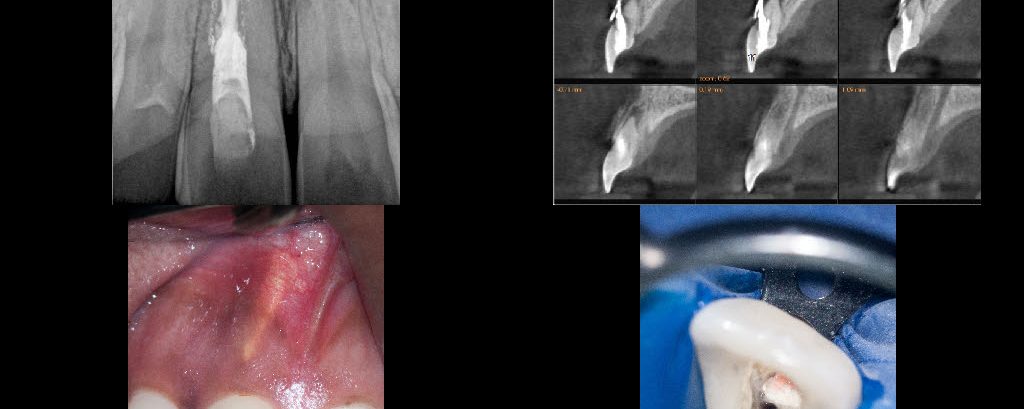

Perforation management

23 YF presented with pain and clinical signs of GP inside the buccal aspect of the gingiva around tooth #11 (FDI). The scan shows the buccal perforation with two GP points and an apical finding. Initially we removed all GP fragments internally and repaired the internal aspect of the perforation with SDR and interim CaOH […]